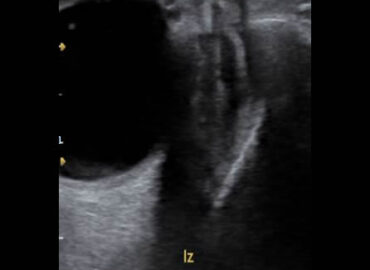

Paciente de 14 años de edad, que consulta por edema palpebral izquierdo de 15 dias de evolucion.

Edema palpebral de ojo izquierdo